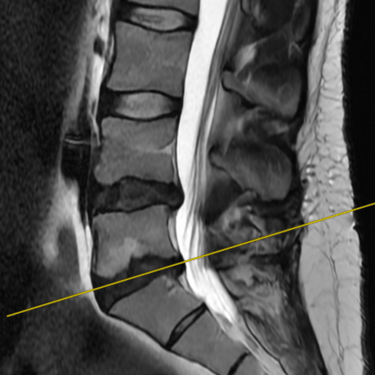

La discopatía degenerativa lumbar es una de las principales causas de dolor lumbar crónico. Se caracteriza por la pérdida de altura discal, deshidratación y cambios en las superficies vertebrales adyacentes. En la resonancia magnética (RMN) se identifican los cambios Modic, que reflejan alteraciones inflamatorias y degenerativas en el hueso subcondral: tipo I (edema), tipo II (grasa) y tipo III (esclerosis). Estos hallazgos permiten correlacionar el dolor lumbar con la patología discal y orientar un tratamiento personalizado. La RMN es, por tanto, una herramienta esencial para el diagnóstico preciso y la planificación terapéutica en pacientes con esta condición.